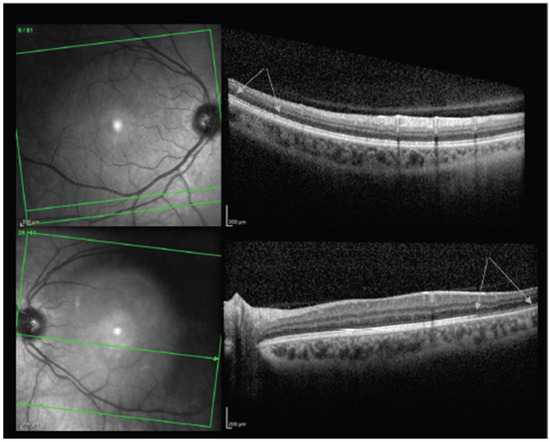

8.1. Acute Macular Neuroretinopathy

- Bohler, A.D.; Strom, M.E.; Sandvig, K.U.; Moe, M.C.; Jorstad, O.K. Acute macular neuroretinopathy following COVID-19 vaccination. Eye 2021, 1–2. [Google Scholar] [CrossRef]

- Mambretti, M.; Huemer, J.; Torregrossa, G.; Ullrich, M.; Findl, O.; Casalino, G. Acute Macular Neuroretinopathy following Coronavirus Disease 2019 Vaccination. Ocul. Immunol. Inflamm. 2021, 29, 730–733. [Google Scholar] [CrossRef] [PubMed]

- Chen, S.; Hodge, C. Comment on: Acute macular neuroretinopathy following COVID-19 vaccination. Eye 2021. [Google Scholar] [CrossRef] [PubMed]

- Pichi, F.; Aljneibi, S.; Neri, P.; Hay, S.; Dackiw, C.; Ghazi, N.G. Association of Ocular Adverse Events with Inactivated COVID-19 Vaccination in Patients in Abu Dhabi. JAMA Ophthalmol. 2021, 139, 1131–1135. [Google Scholar] [CrossRef] [PubMed]

- Book, B.A.J.; Schmidt, B.; Foerster, A.M.H. Bilateral Acute Macular Neuroretinopathy after Vaccination against SARS-CoV-2. JAMA Ophthalmol. 2021, 139, e212471. [Google Scholar] [CrossRef]

- Druke, D.; Pleyer, U.; Hoerauf, H.; Feltgen, N.; Bemme, S. Acute macular neuroretinopathy (AMN) following COVID-19 vaccination. Am. J. Ophthalmol. Case Rep. 2021, 24, 101207. [Google Scholar] [CrossRef]

- Valenzuela, D.A.; Groth, S.; Taubenslag, K.J.; Gangaputra, S. Acute macular neuroretinopathy following Pfizer-BioNTech COVID-19 vaccination. Am. J. Ophthalmol. Case Rep. 2021, 24, 101200. [Google Scholar] [CrossRef]

| Book et al., 2021 | 21 | F | AZD1222, #1 | 3 | 20/16 | OD | Bilateral paracentral scotomas with underlying circumscribed paracentral dark lesions on exam, OCT with outer plexiform layer thickening and discontinuity, diagnosed as bilateral AMN. |

| Drüke et al., 2021 | 23 | F | AZD1222, #1 | 1 | 20/20 | OD | Development of bilateral paracentral scotomas. Fundus photography revealed a subtle brownish rimmed lesion parafoveally OD and blurred lesion nasal to the macula OS. IR and OCT imaging confirmed a diagnosis of AMN. |

| Mambretti et al., 2021 | 22 | F | AZD1222, #1 | 2 | 20/20 | OD | Acute paracentral scotoma OD with barely visible parafoveal lesions on fundus exam. OCT was consistent with AMN. |

| 28 | F | AZD1222, #1 | 2 | 20/20 | OD | Acute paracentral scotoma OD with OCT consistent with AMN. | |

| Michel et al., 2021 | 21 | F | AZD1222, #1 | 2 | 20/20 | OS | Acute-onset of 4 central scotomas OS, well-demarcated dark oval-shaped areas surrounding the left fovea on infrared imaging. OCT with multifocal highly reflective lesions and with ellipsoid and interdigitation zone disruption consistent with AMN. |